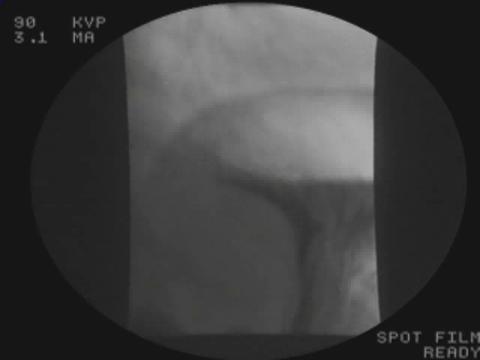

Bolo baritato: fluoroscopia

La fluoroscopia (tecnica radiografica continua) trova impiego per visualizzare l’esofago dopo l’ingestione di bario liquido.

In questo video, l’esofago si contrae al passaggio del bario attraverso di esso, nello stomaco e nell’intestino tenue.

(Il video è privo di audio.)

Per gentile concessione del Dott. Howard Lee.